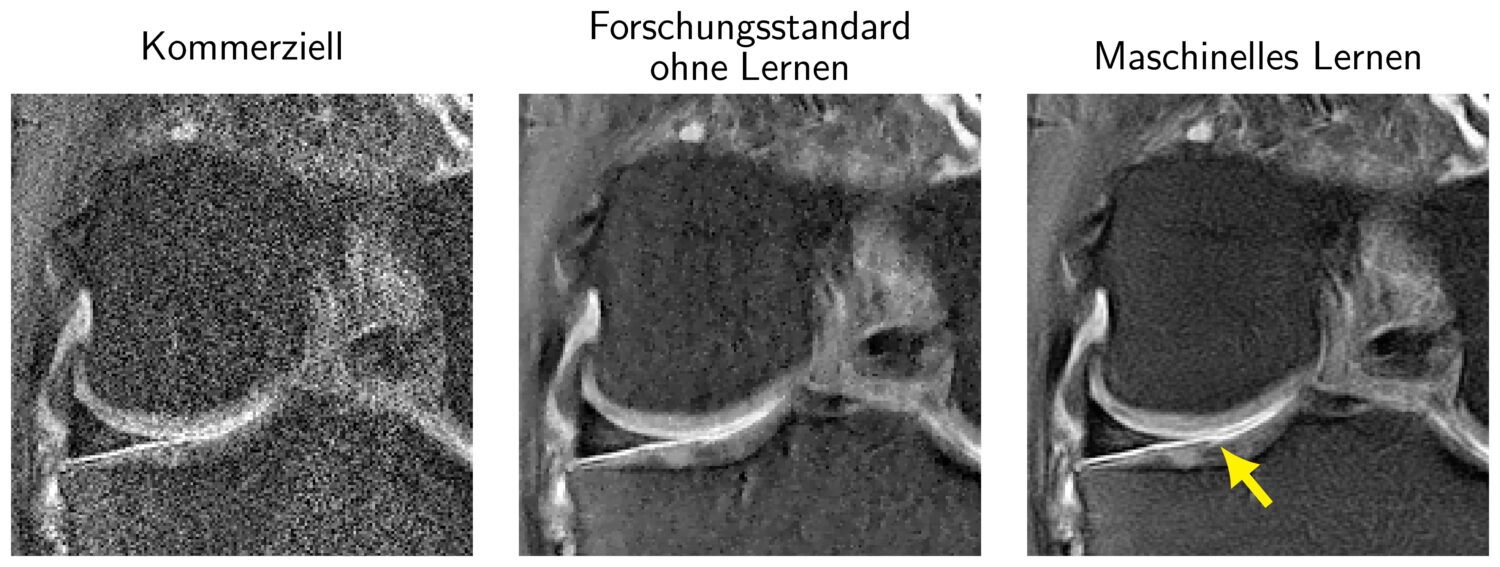

Die „Vision, Learning and Optimization“-Arbeitsgruppe um Thomas Pock hat in den letzten Jahren an der TU Graz sogenannte „Variationsnetzwerke“ (VNs) entwickelt, welche die Vorteile von traditionellen mathematischen Variationsmethoden und Deep-Learning-Methoden vereinen. In einer Zusammenarbeit mit Florian Knoll an der NYU School of Medicine wurden diese VNs auf das Problem der MRT-Rekonstruktion angewandt. Die Dissertation von Kerstin Hammernik sowie der in diesem Rahmen verfasste Artikel, der seit 2018 knapp 600-mal zitiert wurde, dient als Grundlage für internationale Forschungsprojekte, wie etwa die Kooperation mit Facebook AI Research am Projekt fastMRI. Als Open-Source-Projekt hat fastMRI seine Daten, Modelle und Codes veröffentlicht, damit andere Forscher*innen auf ihrer Arbeit aufbauen und neue Ideen einbringen können. Dieser offene Ansatz soll Fortschritte bei der klinischen Implementierung ermöglichen und zu neuen Möglichkeiten führen, MRT-Scans mit KI zu beschleunigen.